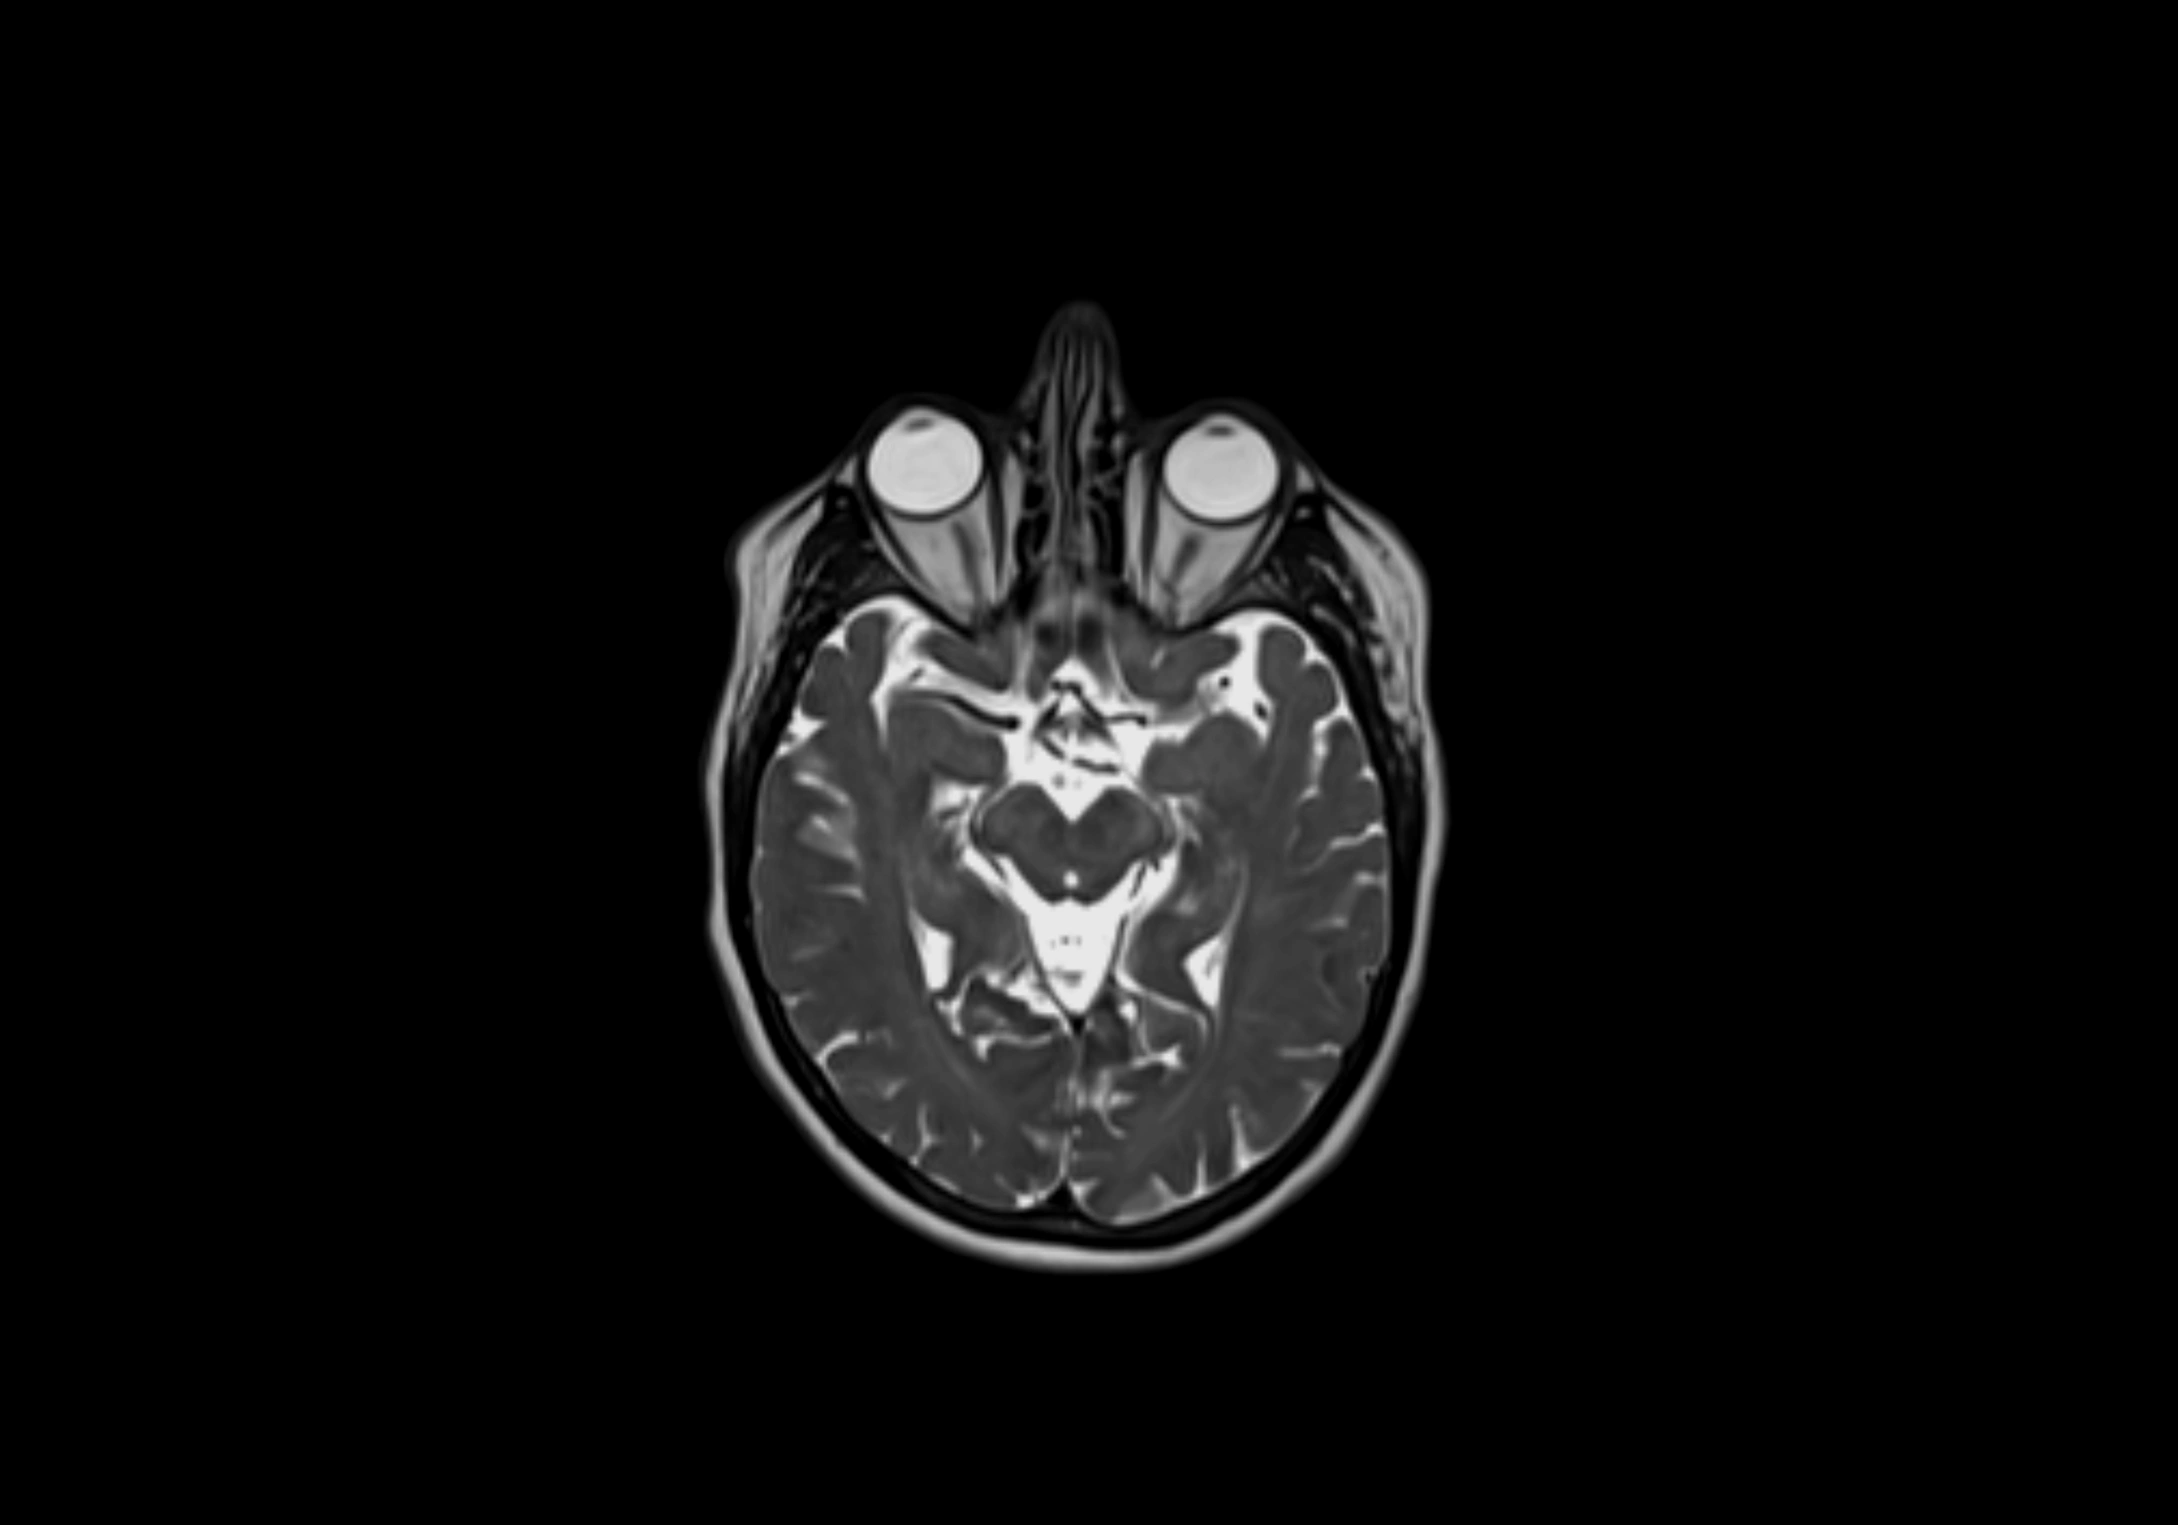

MRI Appearance

T1-weighted images:

• Normal accessory nodes appear as small, oval hypointense to intermediate signal structures within subcutaneous fat

• Surrounded by hyperintense fat, enhancing contrast for visualization

• Pathological nodes may appear enlarged or rounded, sometimes with cortical thickening

T2-weighted images:

• Nodes show intermediate signal, with surrounding fat bright

• Useful for detecting edema, inflammation, or infiltration

• Fatty hilum may appear slightly hyperintense relative to cortex